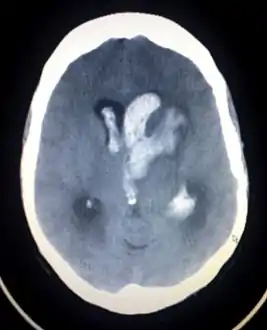

![]() تصوير مقطعي محوسب لنزف داخل القحف تصوير مقطعي محوسب لنزف داخل القحف | |

يمكن تمييز النزف داخل المتن باستخدام التصوير الطبقي المحوسب بسبب ظهور الدم بلون نيّر أكثر من النسج الأخرى وكونه منعزلًا عن اللوحة الداخلية للجمجمة بالنسيج الدماغي. غالبًا ما يكون النسيج المحيط بالنزف بلون أقل كثافة من بقية الدماغ بسبب الوذمة، وبالتالي يظهر بلون أغمق في التصوير الطبقي المحوسب.[14]